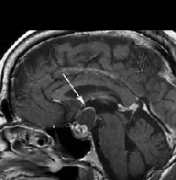

【颅咽管瘤赴德手术案例】颅咽管瘤三次手术后反复发作,赴德手术终获全切,术后半年未复发。经历了千辛万苦的治疗,却又功亏一篑肿瘤复发,对于任...

颅咽管瘤手术后复发,此时应该重复手术还是放疗?复发性颅咽管瘤的治疗选择包括重复手术、放射治疗、放射外科和囊内治疗。我们报告了在1991年至20...

在一项大的系列研究中,60%~93%的患者10年没有复发生存,10年生存率达64%~96%,与颅咽管瘤复发相关的较有意义的因素是手术切除范围。颅咽管瘤到底能完全根...